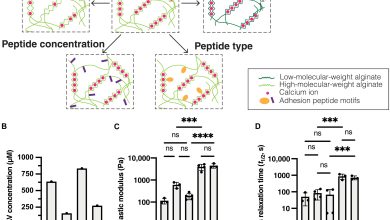

O gel baseado em algas oferece nova ferramenta para pesquisa de câncer de mama

Os EBMs modificados têm propriedades mecânicas e bioquímicas independentes. Crédito: Avanços científicos (2025). Doi: 10.1126/sciadv.adx2110 Em 2020, bem quando Jane…